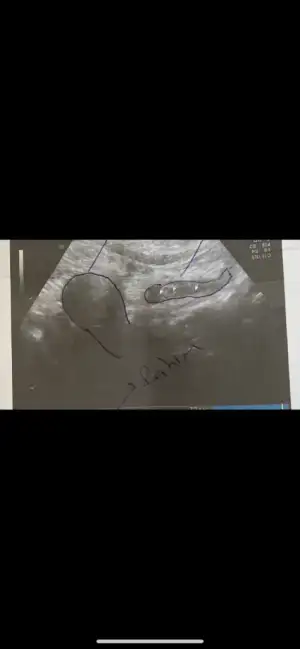

Kızlar selam, şimdiye kadar bulantı dışında bi belirtim yoktu ama 11+4 üm 2 gündür karın ağrım ve meme dolgunluğum arttı , emzirdiğim için sanırım memelerim şişmemişti sadece arada bıçak batması oluyordu ama şimdi belirgin bi şekilde dolgunluk var, uygulamaya göre de adet dönemindeyim vücut kendini ona göre adapte ettiği için adet dönemlerimizde eskiye benzer sancılarımız olabiliyormuş..

Belirtilerim yok demeyim anın tanını çıkarın her an her şey olabiliyor